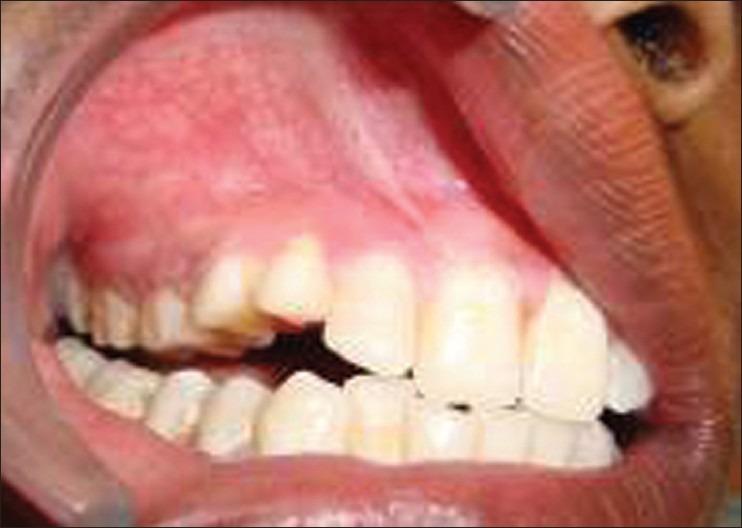

Hemangiomatous ameloblastoma (HA), which is a rare ameloblastic variant, is presented in a 15-year-old boy in the maxillary right molar region associated with unerupted canine and premolars. Radiologic and computed tomographic analysis was suggestive of cystic lesion. An histology picture confirmed the diagnosis of HA. There are less than eight cases documented in the literature and mostly are in the middle age with mandibular location. This is first ever reported case of HA in a 15-year-old boy with maxillary location. Due to less number of documented cases and no long-term follow-ups, clinical behavior and prognosis of this lesion are uncertain. In this case report, the clinical, histological, and radiographic features of HA are presented.

血管瘤样成釉细胞瘤(HA)是一种罕见的成釉细胞变异型,发生于一名15岁男孩的右上颌磨牙区,与未萌出的尖牙和前磨牙相关。放射学和计算机断层扫描分析提示为囊性病变。组织学图像确诊为HA。文献记载的病例少于8例,大多数发生于中年,位于下颌骨。这是首次报道的发生于15岁上颌骨的HA病例。由于记录在案的病例数量较少且缺乏长期随访,该病变的临床行为和预后尚不确定。本病例报告展示了HA的临床、组织学和影像学特征。